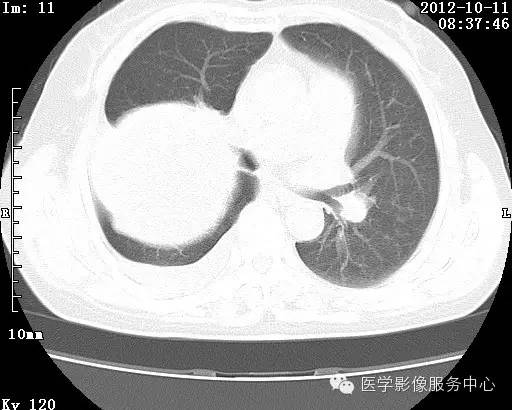

【病例】右肺巨大错构瘤1例CT影像表现

病史:女 65岁咳嗽咳痰 右肺巨大肿块就诊。

错构瘤的主要组织成分包括软骨、脂肪、平滑肌、腺体、上皮细胞,有时还有骨组织或钙化。错构瘤一般为实质致密的球形、卵圆形,也可以是分叶状或结节状,大多数直径在3cm以下。

错构瘤的发病年龄多数在40岁以上,男性多于女性。 绝大多数错构瘤(约80%以上)生长在肺的周边部,紧贴于肺的脏层胸膜之下,有时突出于肺表面。其特征钙化为爆米花样钙化,内有脂肪软骨成分等等。最常见的部位是胸膜下肺实质内,其次为主支气管或肺叶、肺段支气管内。